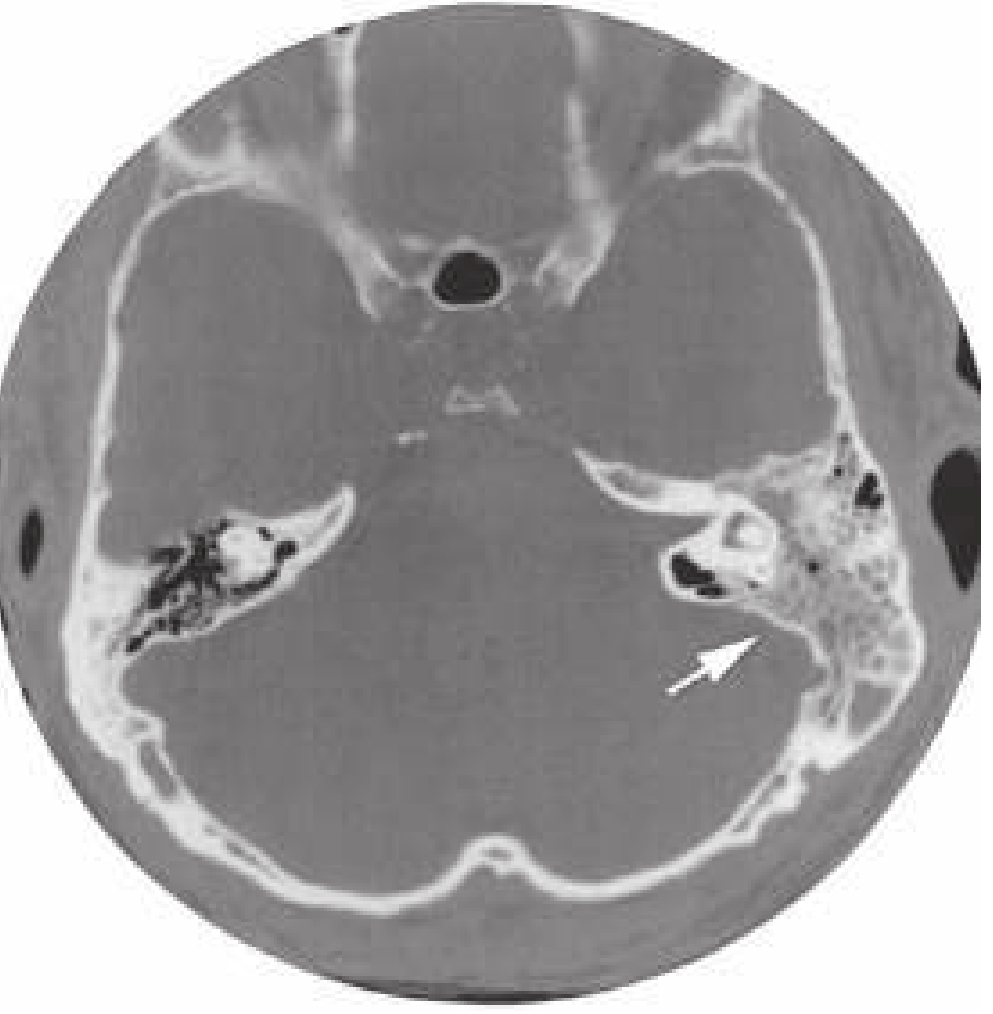

CT scan of acute mastoiditis showing opacification of the left mastoid air cells (arrow)

CT scan of acute mastoiditis — note opacification of the left mastoid air cells (arrow). — Rosen's Emergency Medicine